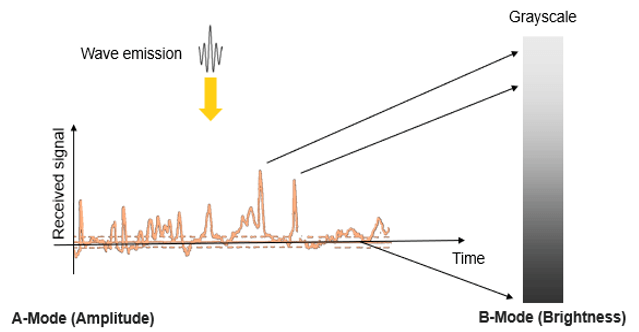

A-Mode

Different ultrasound modes are used in medical imaging today. The A-Mode, or Amplitude Modulation, was the first discovered mode. It is the display of amplitude spikes of different heights, where it consists of an X and Y axes. The X-axis represents the depth, while the Y-axis represents the Amplitude. This image shows an example of the A-Mode display.

B-Mode

The B-Mode, or Brightness Modulation, is the most common form of ultrasound imaging. It is the display of a 2D map of B-Mode data. The B-Mode is based on the brightness which depends on the intensity of the returning echo. In the B-Mode, there is a Z-axis, which represents the echo intensity or amplitude in function of the depth. The B-Mode will display an image of large and small dots, representing strong and weak echoes respectively.

The amplitude of the echo modulates the gray level of a video monitor. This mode allows the representation of ultrasound data collected in a 2-dimensional image.